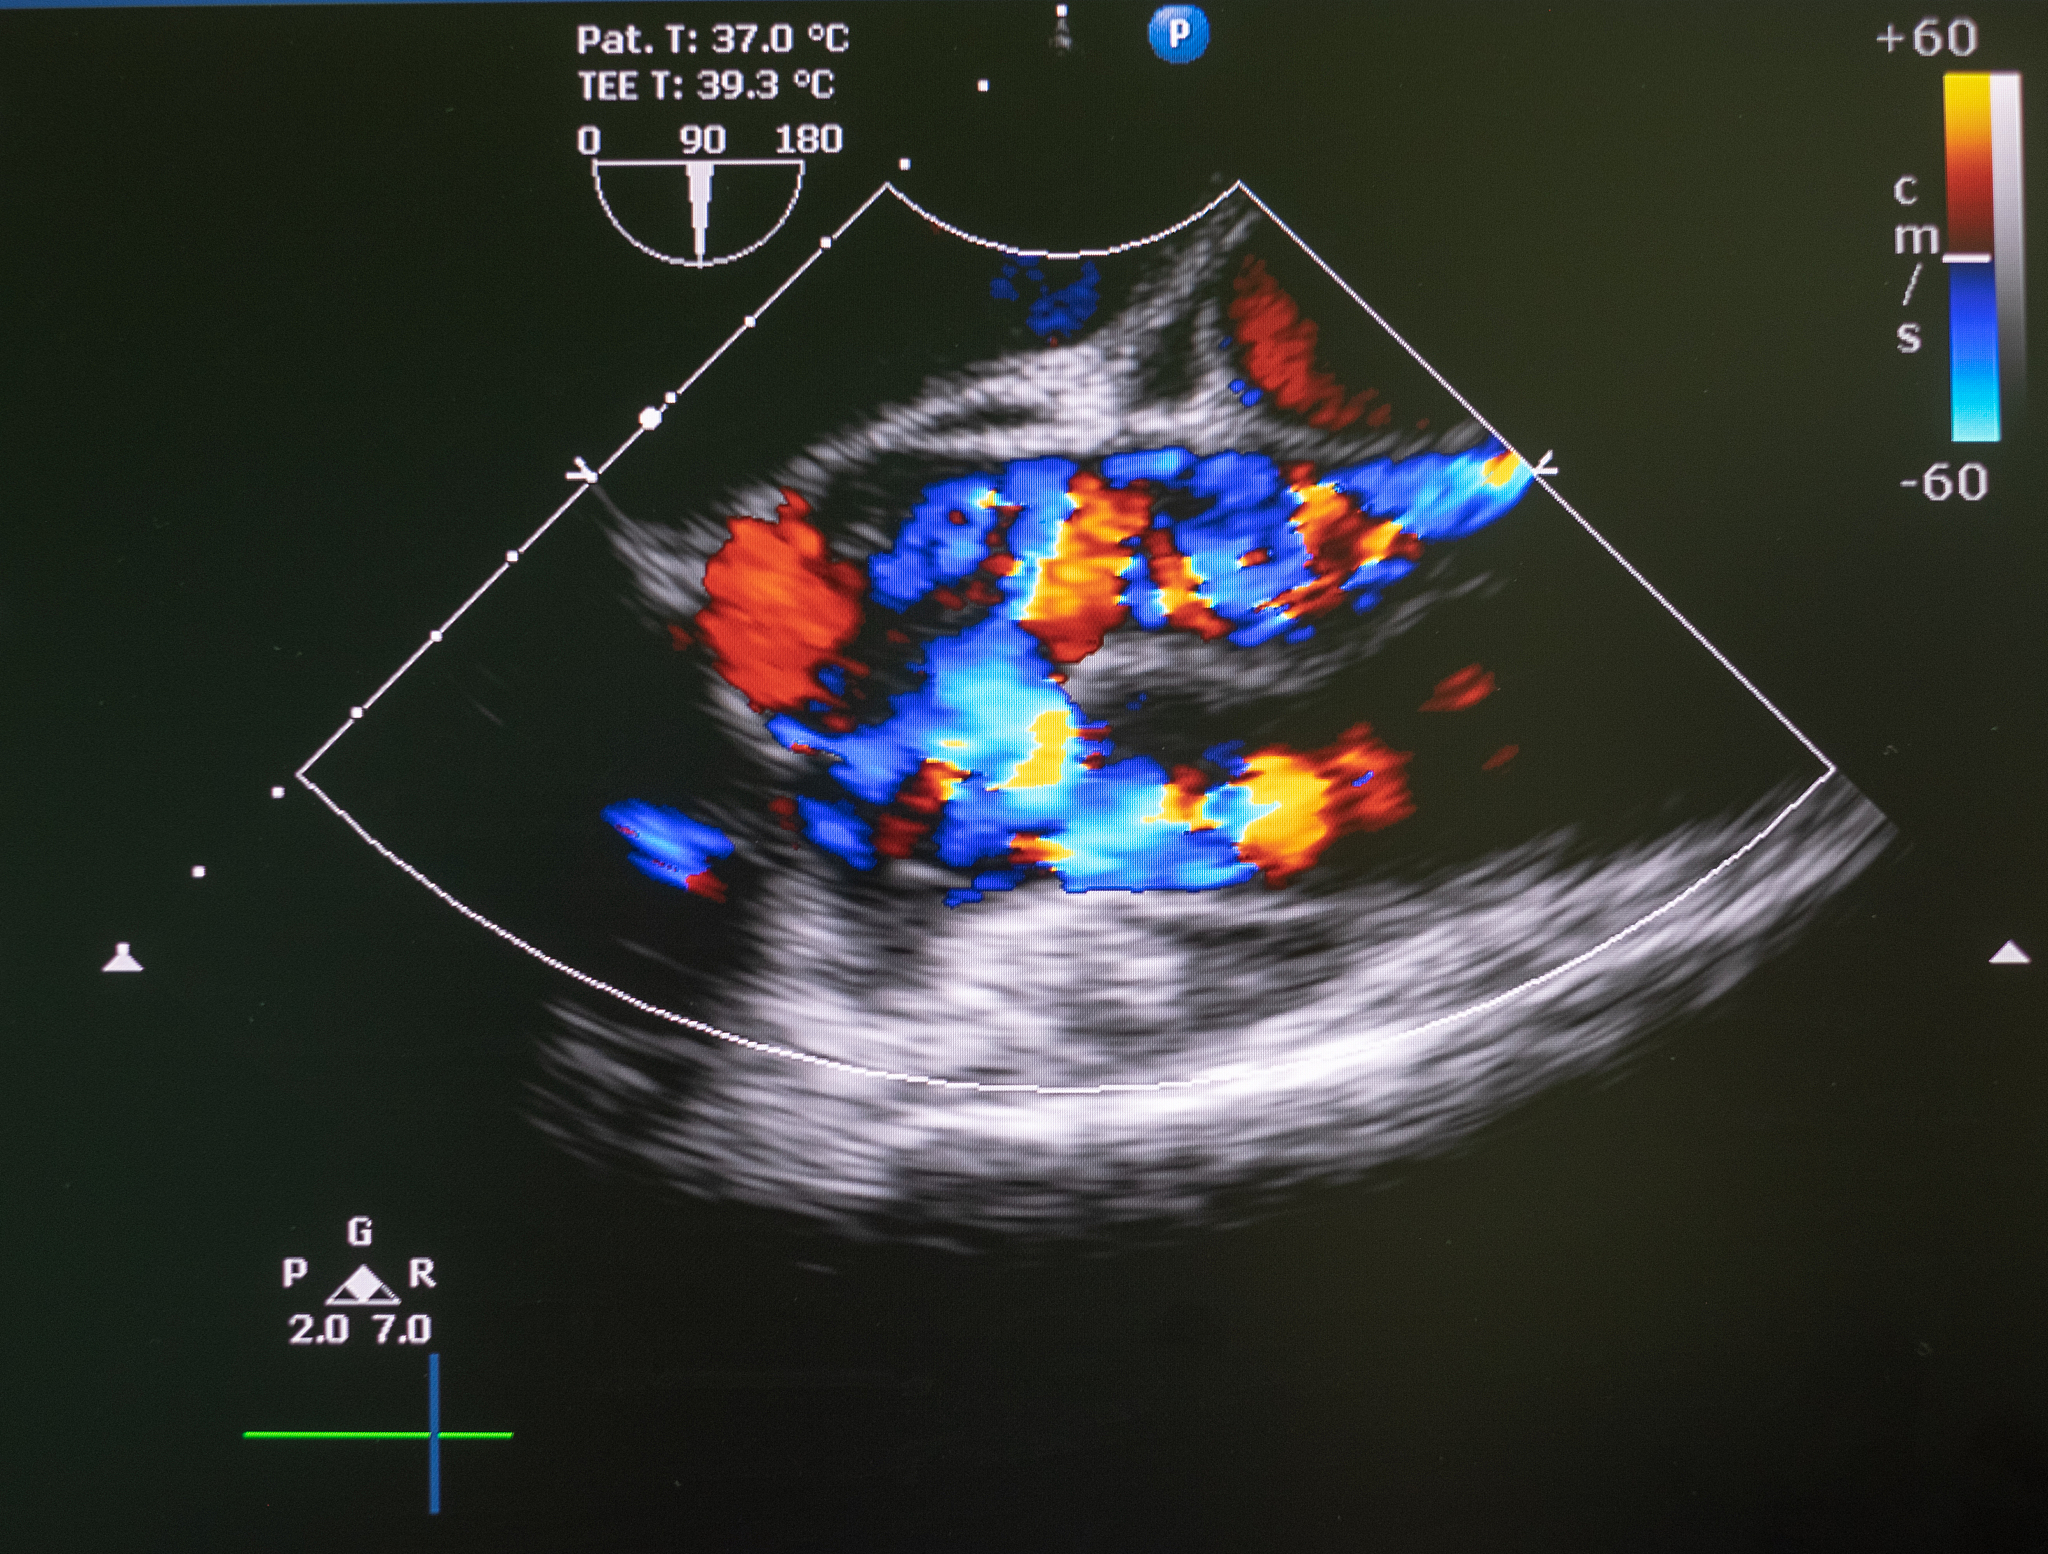

Routine ultrasound examination: A slightly 'hypoechoic' plaque is observed at the bifurcation of the right common carotid artery to the beginning of the internal carotid artery, leading to stenosis of the starting segment of the internal carotid artery. The maximum flow velocity at the stenosis is about 272cm/s, and the flow velocity near the proximal end of the stenosis is about 81cm/s. The PSVICA/PSVCCA is 3.36. According to the NASCET standard, the diameter stenosis rate is approximately 58.4%. A low 'hypoechoic' attachment is faintly visible at the distal end of the plaque, which shows slight movement with the pulsation of the carotid artery. The color Doppler also shows a suspicious filling defect.